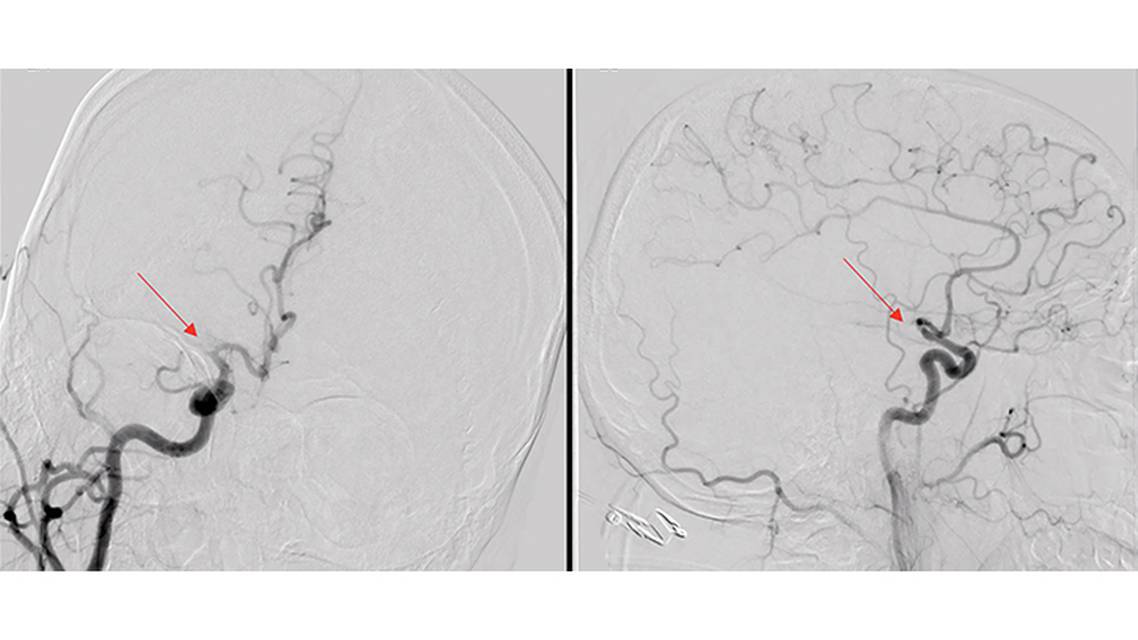

Acute ischemic stroke is a potentially life-threatening neurologic manifestation of infection with the SARS-CoV-2 virus that causes COVID-19.1,2 The pathophysiology of unusual COVID-19–related cerebrovascular insults is presumed to be related to multiple factors, including a systemic hyperinflammatory and hypercoagulable state.3 Cerebral ischemic events have been described in COVID-19, often in patients under age 50, and sometimes without identifiable cerebrovascular risk factors. Some also present with evidence of large vessel occlusion (LVO).4 We demonstrate a unique and atypical case of acute ischemic stroke secondary to focal vasculopathy without evidence of hypercoagulability in a young patient with COVID-19, requiring mechanical thrombectomy and emergent intracranial stenting. We also review the currently available literature on COVID-19–related neurovascular events.

There have been 2 atypical reports of children with focal central nervous system arteriopathy with resultant ischemic strokes due to COVID-19.16,17 The first, age 12 years, had new-onset seizures and an acute subcortical left middle cerebral artery territory infarction. MRI demonstrated focal vasculopathy of the proximal M1 segment. The second case was age 13 years with headaches and fluctuating right-sided weakness, who was found to have left middle cerebral artery territory infarcts in the frontal and parietal lobes. Corresponding MRI vessel wall imaging was consistent with focal vasculitis of the left M1 segment. Neither child was considered a candidate for acute endovascular treatment.

We describe acute treatment of an atypical focal intracranial lesion related to COVID-19–related acute ischemic stroke. Treatment utilized mechanical thrombectomy and emergent intracranial stenting, the latter of which is not routinely used for LVO treatment, although it has been previously described as a potential rescue therapy for refractory atherosclerotic lesions.18 Intracranial stenting is not favored for treatment of other types of progressive vasculopathies or inflammatory vasculitis. In the case described, there was no evidence of associated hypercoagulability, underlying atherosclerotic disease, severe inflammatory response, small vessel disease, or diffuse vasculitis that have been described in association with COVID-19. Considering the successful and timely treatment, CD achieved a good functional neurologic outcome, and has remained symptom free since.

COVID-19–related neurovascular events have been well described, mostly due to underlying hypercoagulable state, systemic inflammation, or diffuse vasculitic process, potentially requiring steroid, antiviral, and anticoagulation therapies. We highlight here another rare but possible COVID-19–related entity of focal intracranial vasculopathy without other underlying abnormalities in an otherwise previously healthy person in their early third decade. We demonstrate successful treatment with an aggressive endovascular approach involving intracranial stenting. An excellent clinical outcome was achieved, and such treatment could be considered for select individuals with refractory focal vasculopathy in the setting of COVID-19.